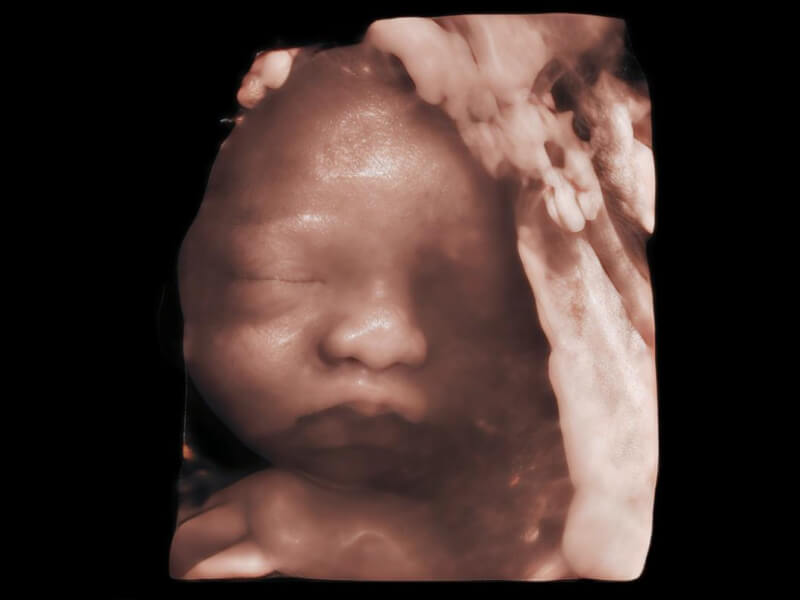

梦溪®P80以“关爱女性”为基石,提供全方位的解决方案,量身定制以满足女性的健康需求,涵盖妇科、生殖健康检查、产前筛查及产后康复等领域。